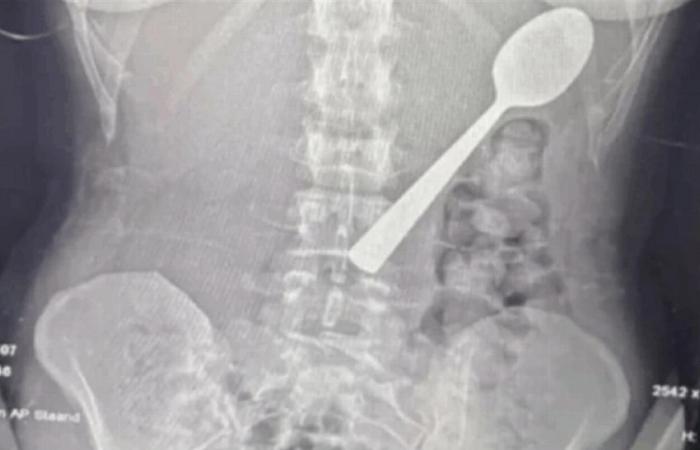

وعند مراجعة الأطباء، تبيّن أن الملعقة أكبر من أن تمر عبر الجهاز الهضمي بشكل طبيعي، ما استدعى تدخلاً عاجلاً. وبعد انتظار يومين تحت المراقبة، خضعت ريمي لعملية منظار معدة تحت التخدير الموضعي، حيث قام الأطباء بتدوير الملعقة بحذر داخل المعدة لسحبها، ما تسبب بنزيف طفيف والتهاب مؤقت في الحلق.